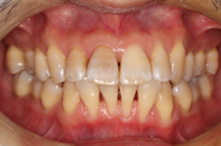

下顎前歯に顕著な歯肉退縮を認める

歯肉退縮が生じることで知覚過敏に繋がるケースは少なくない。また将来的には根面う蝕の可能性も高くなるため、歯肉退縮している場合には予防的な観点から根面被覆手術をした方がいい場合がある。特に知覚過敏が強い場合にはブラッシングがしづらい場合も多くよりう蝕や歯周病のリスクが上がるため注意が必要と考える。